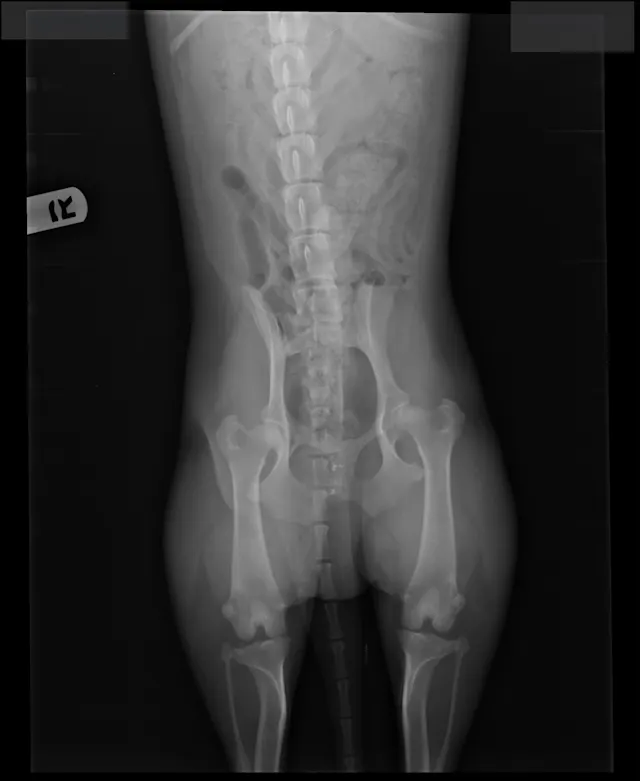

FIGURE 1

Radiographs of Ernest at 8 years of age at a recheck examination